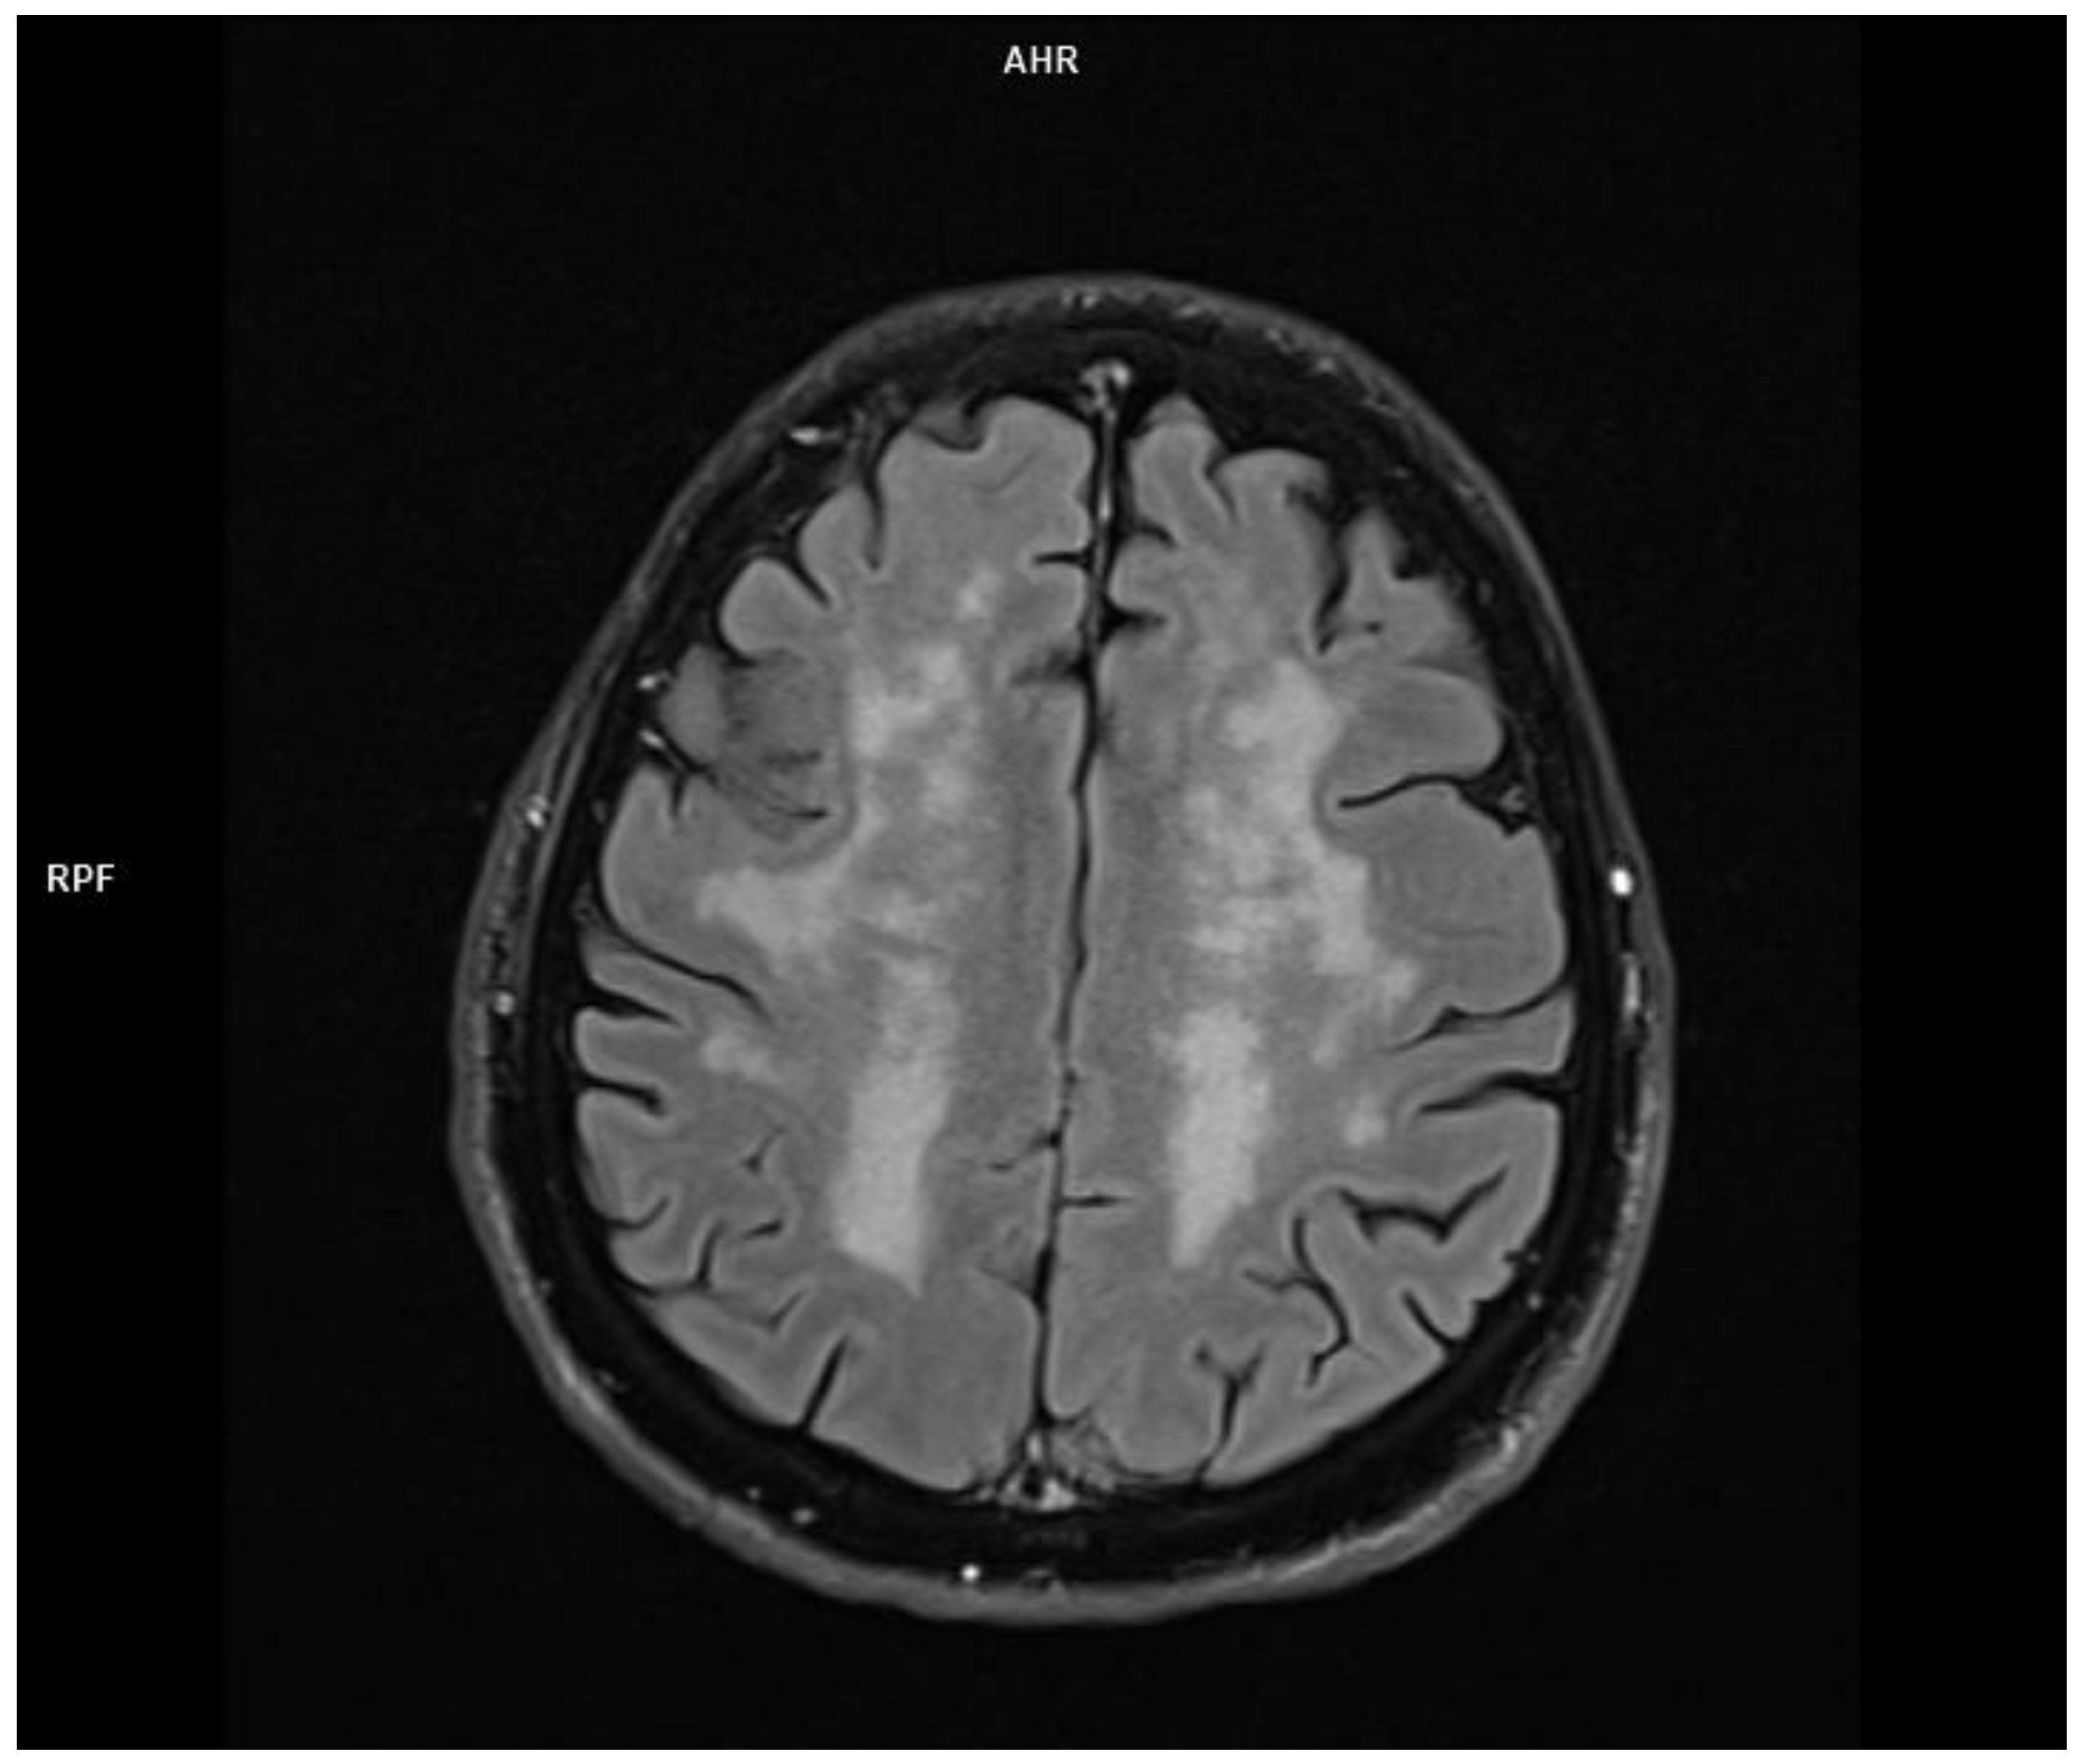

2.1. Patient 1

2.2. Patient 2

2.3. Patient 3